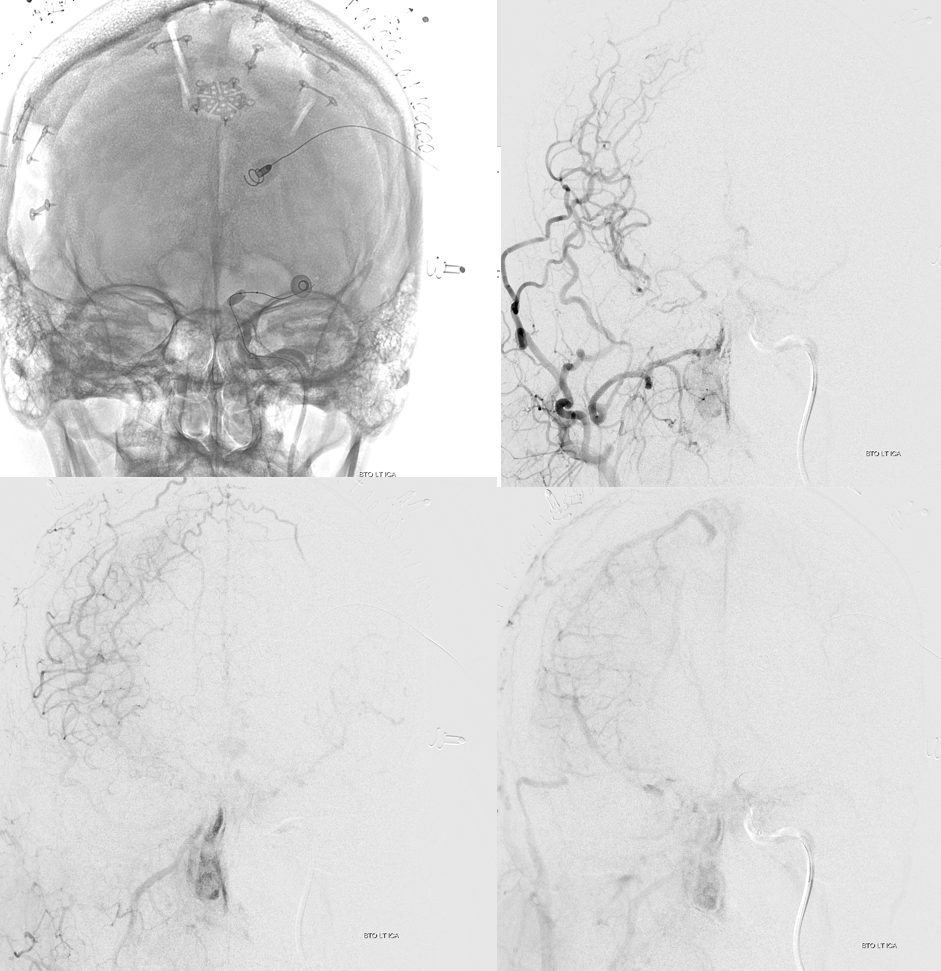

MRA

Robust bypass supports superior division and some more

No aneurysm, as suspected

Stereo pairs

Bypasses. Note A3-A3 patent bypass, as well as STA-MCA. Both seen thru radiolucent skull windows